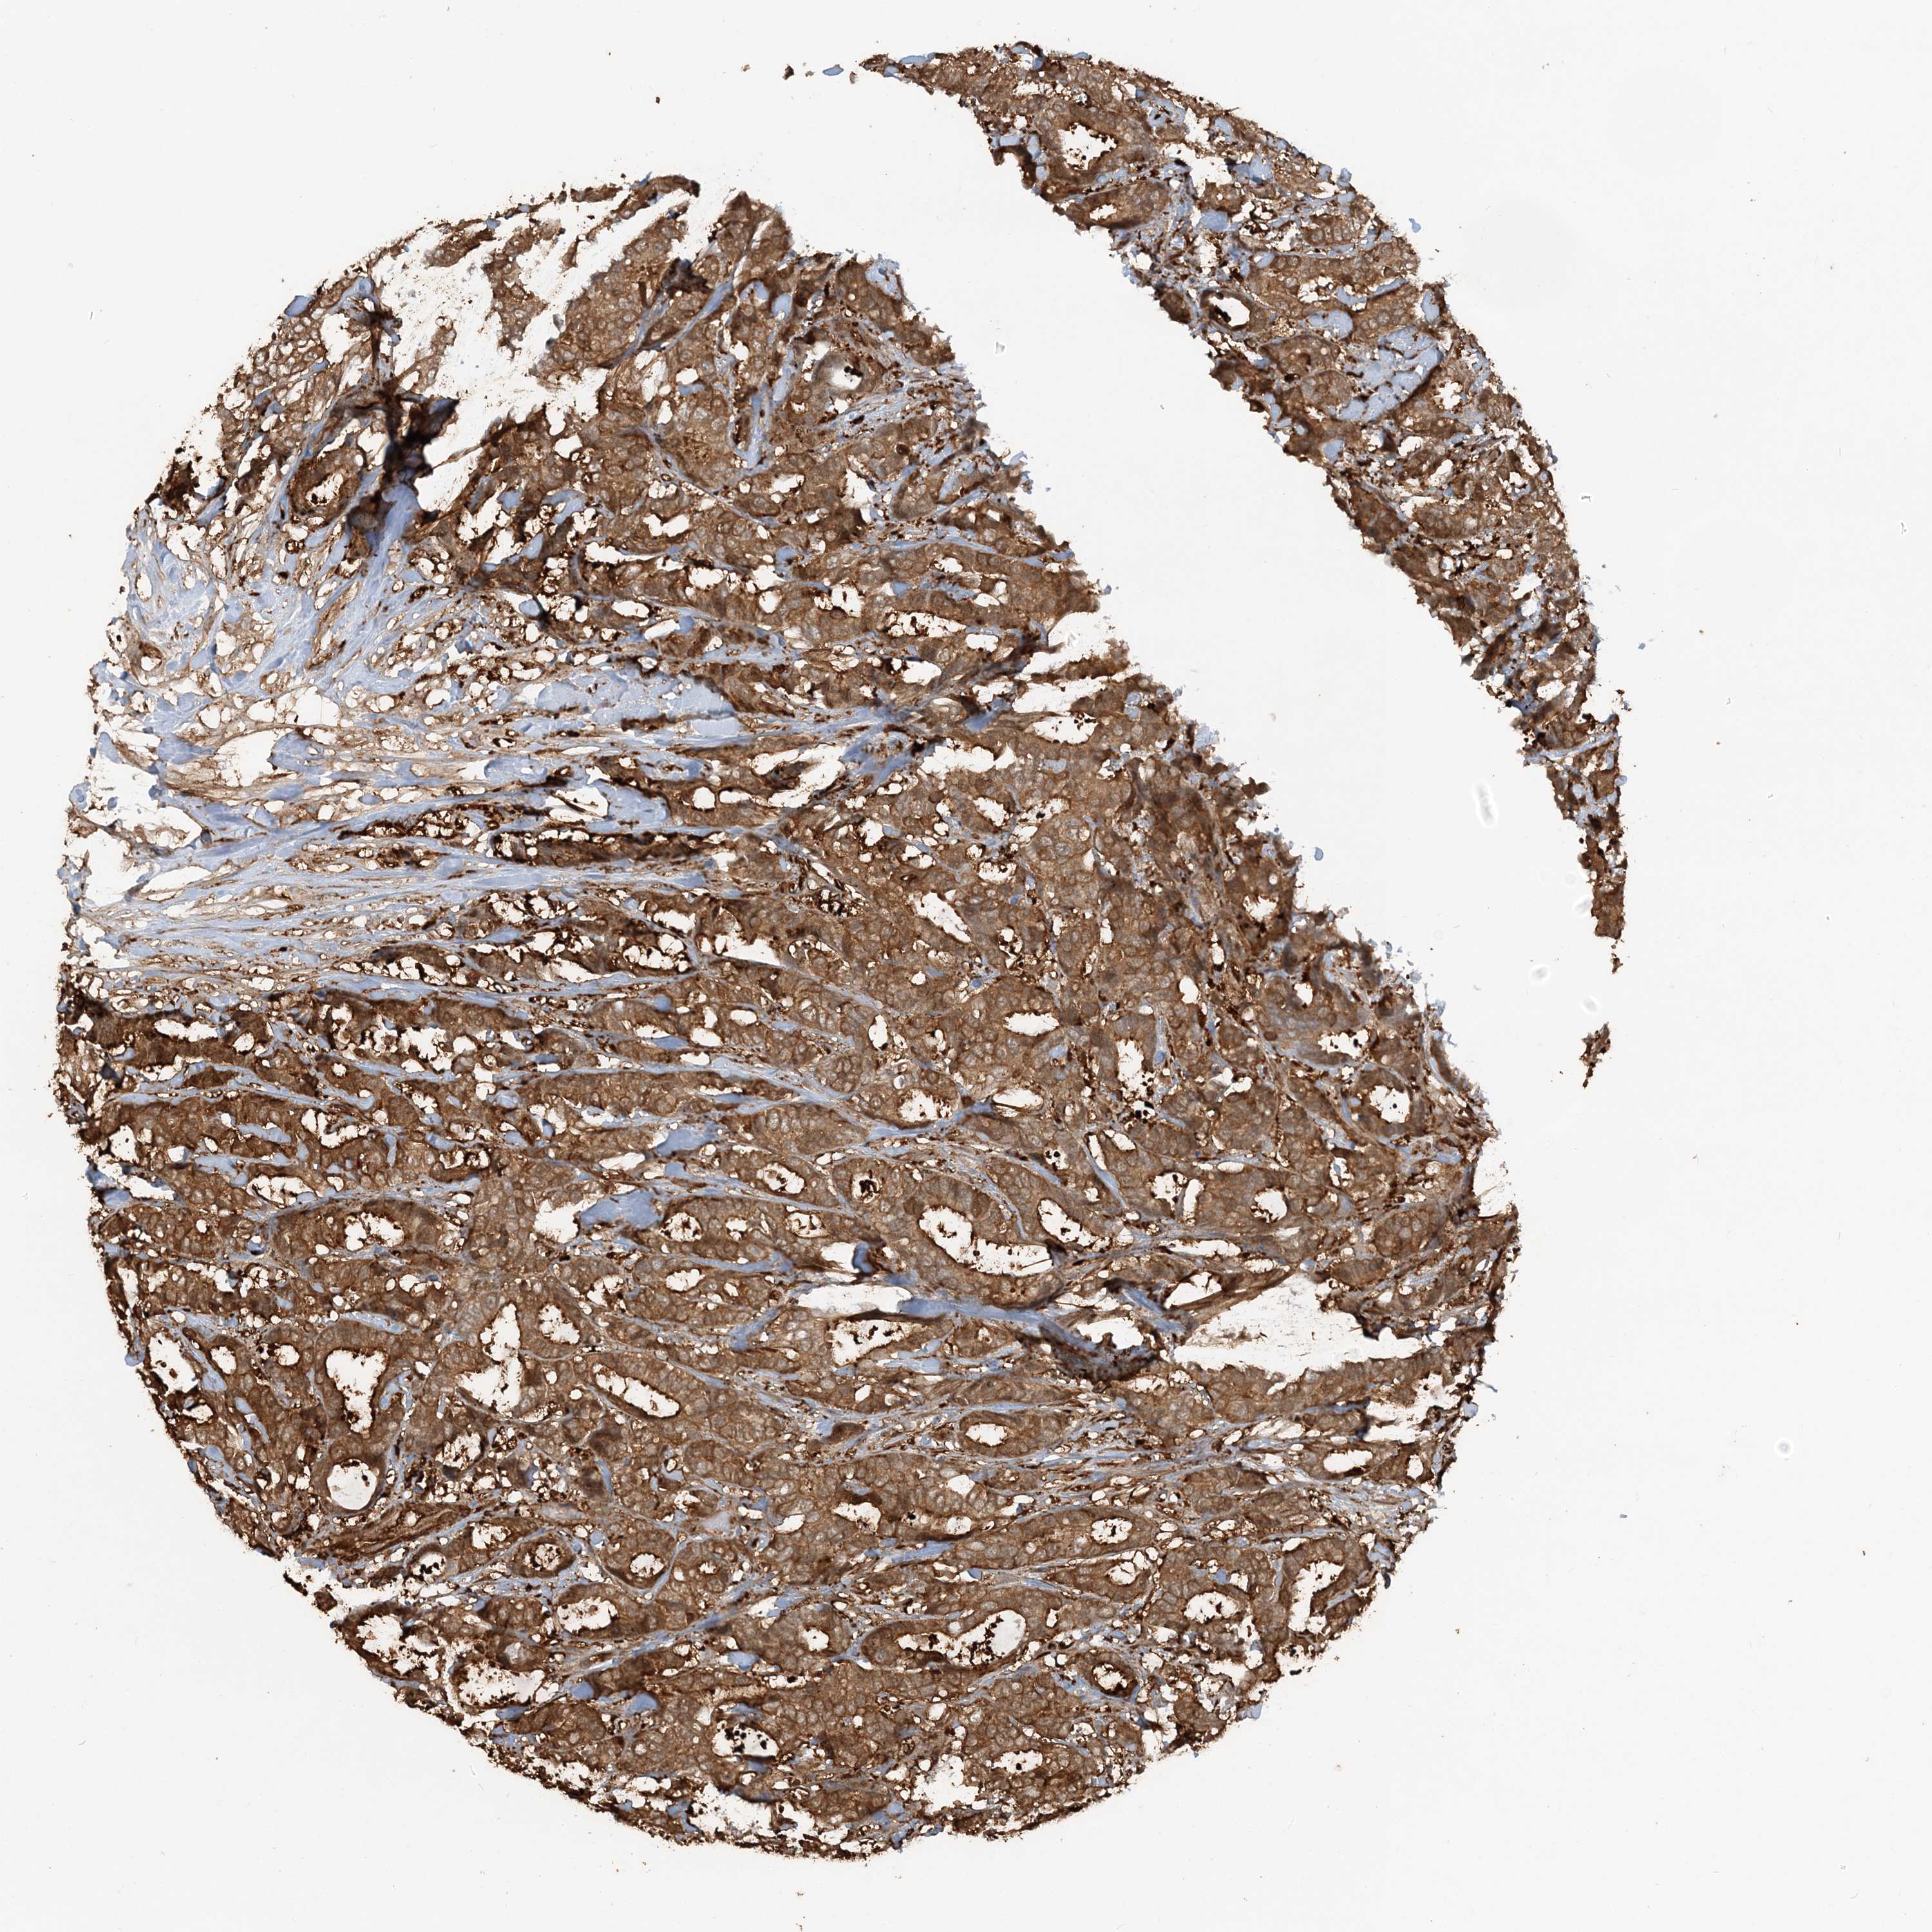

CANCER BREAST CANCER Show tissue menu

BRCA TCGA BRCA VALIDATION PROTEIN EXPRESSION